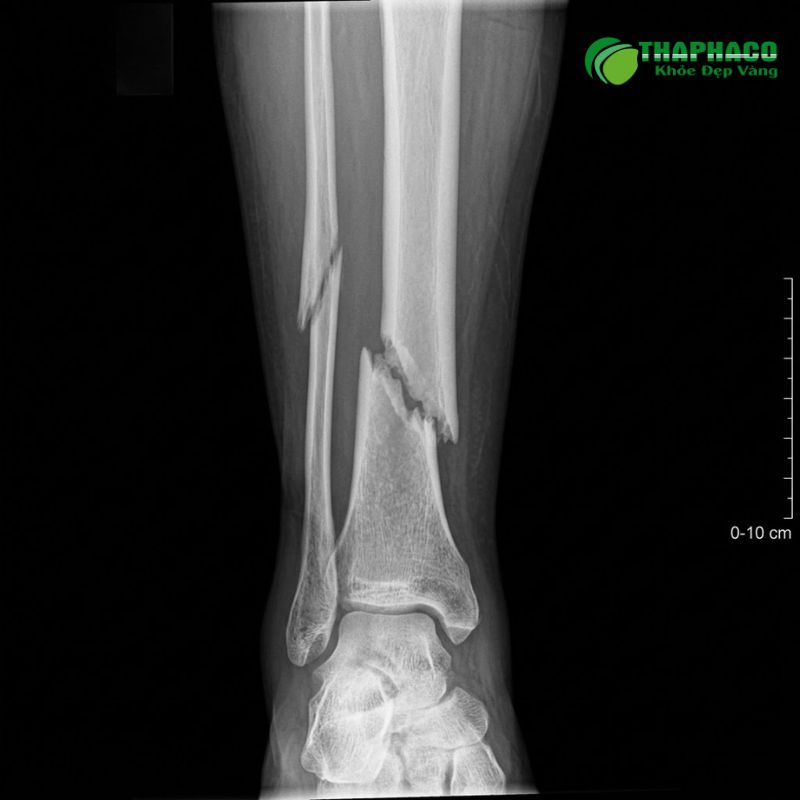

- Chụp X-quang: Đây là phương pháp chẩn đoán hình ảnh cơ bản và quan trọng nhất để xác định vị trí, loại hình gãy xương, mức độ di lệch của các mảnh xương. Thường chụp ít nhất hai tư thế vuông góc.

- Gãy xương hở: Xương gãy làm rách da và mô mềm bên ngoài, xương có thể lòi ra ngoài hoặc vết thương thông với ổ gãy. Loại này rất nguy hiểm vì nguy cơ nhiễm trùng cao và có thể gây biến chứng nghiêm trọng.

- Gãy xương hoàn toàn: Xương bị gãy đứt lìa thành hai hoặc nhiều mảnh.